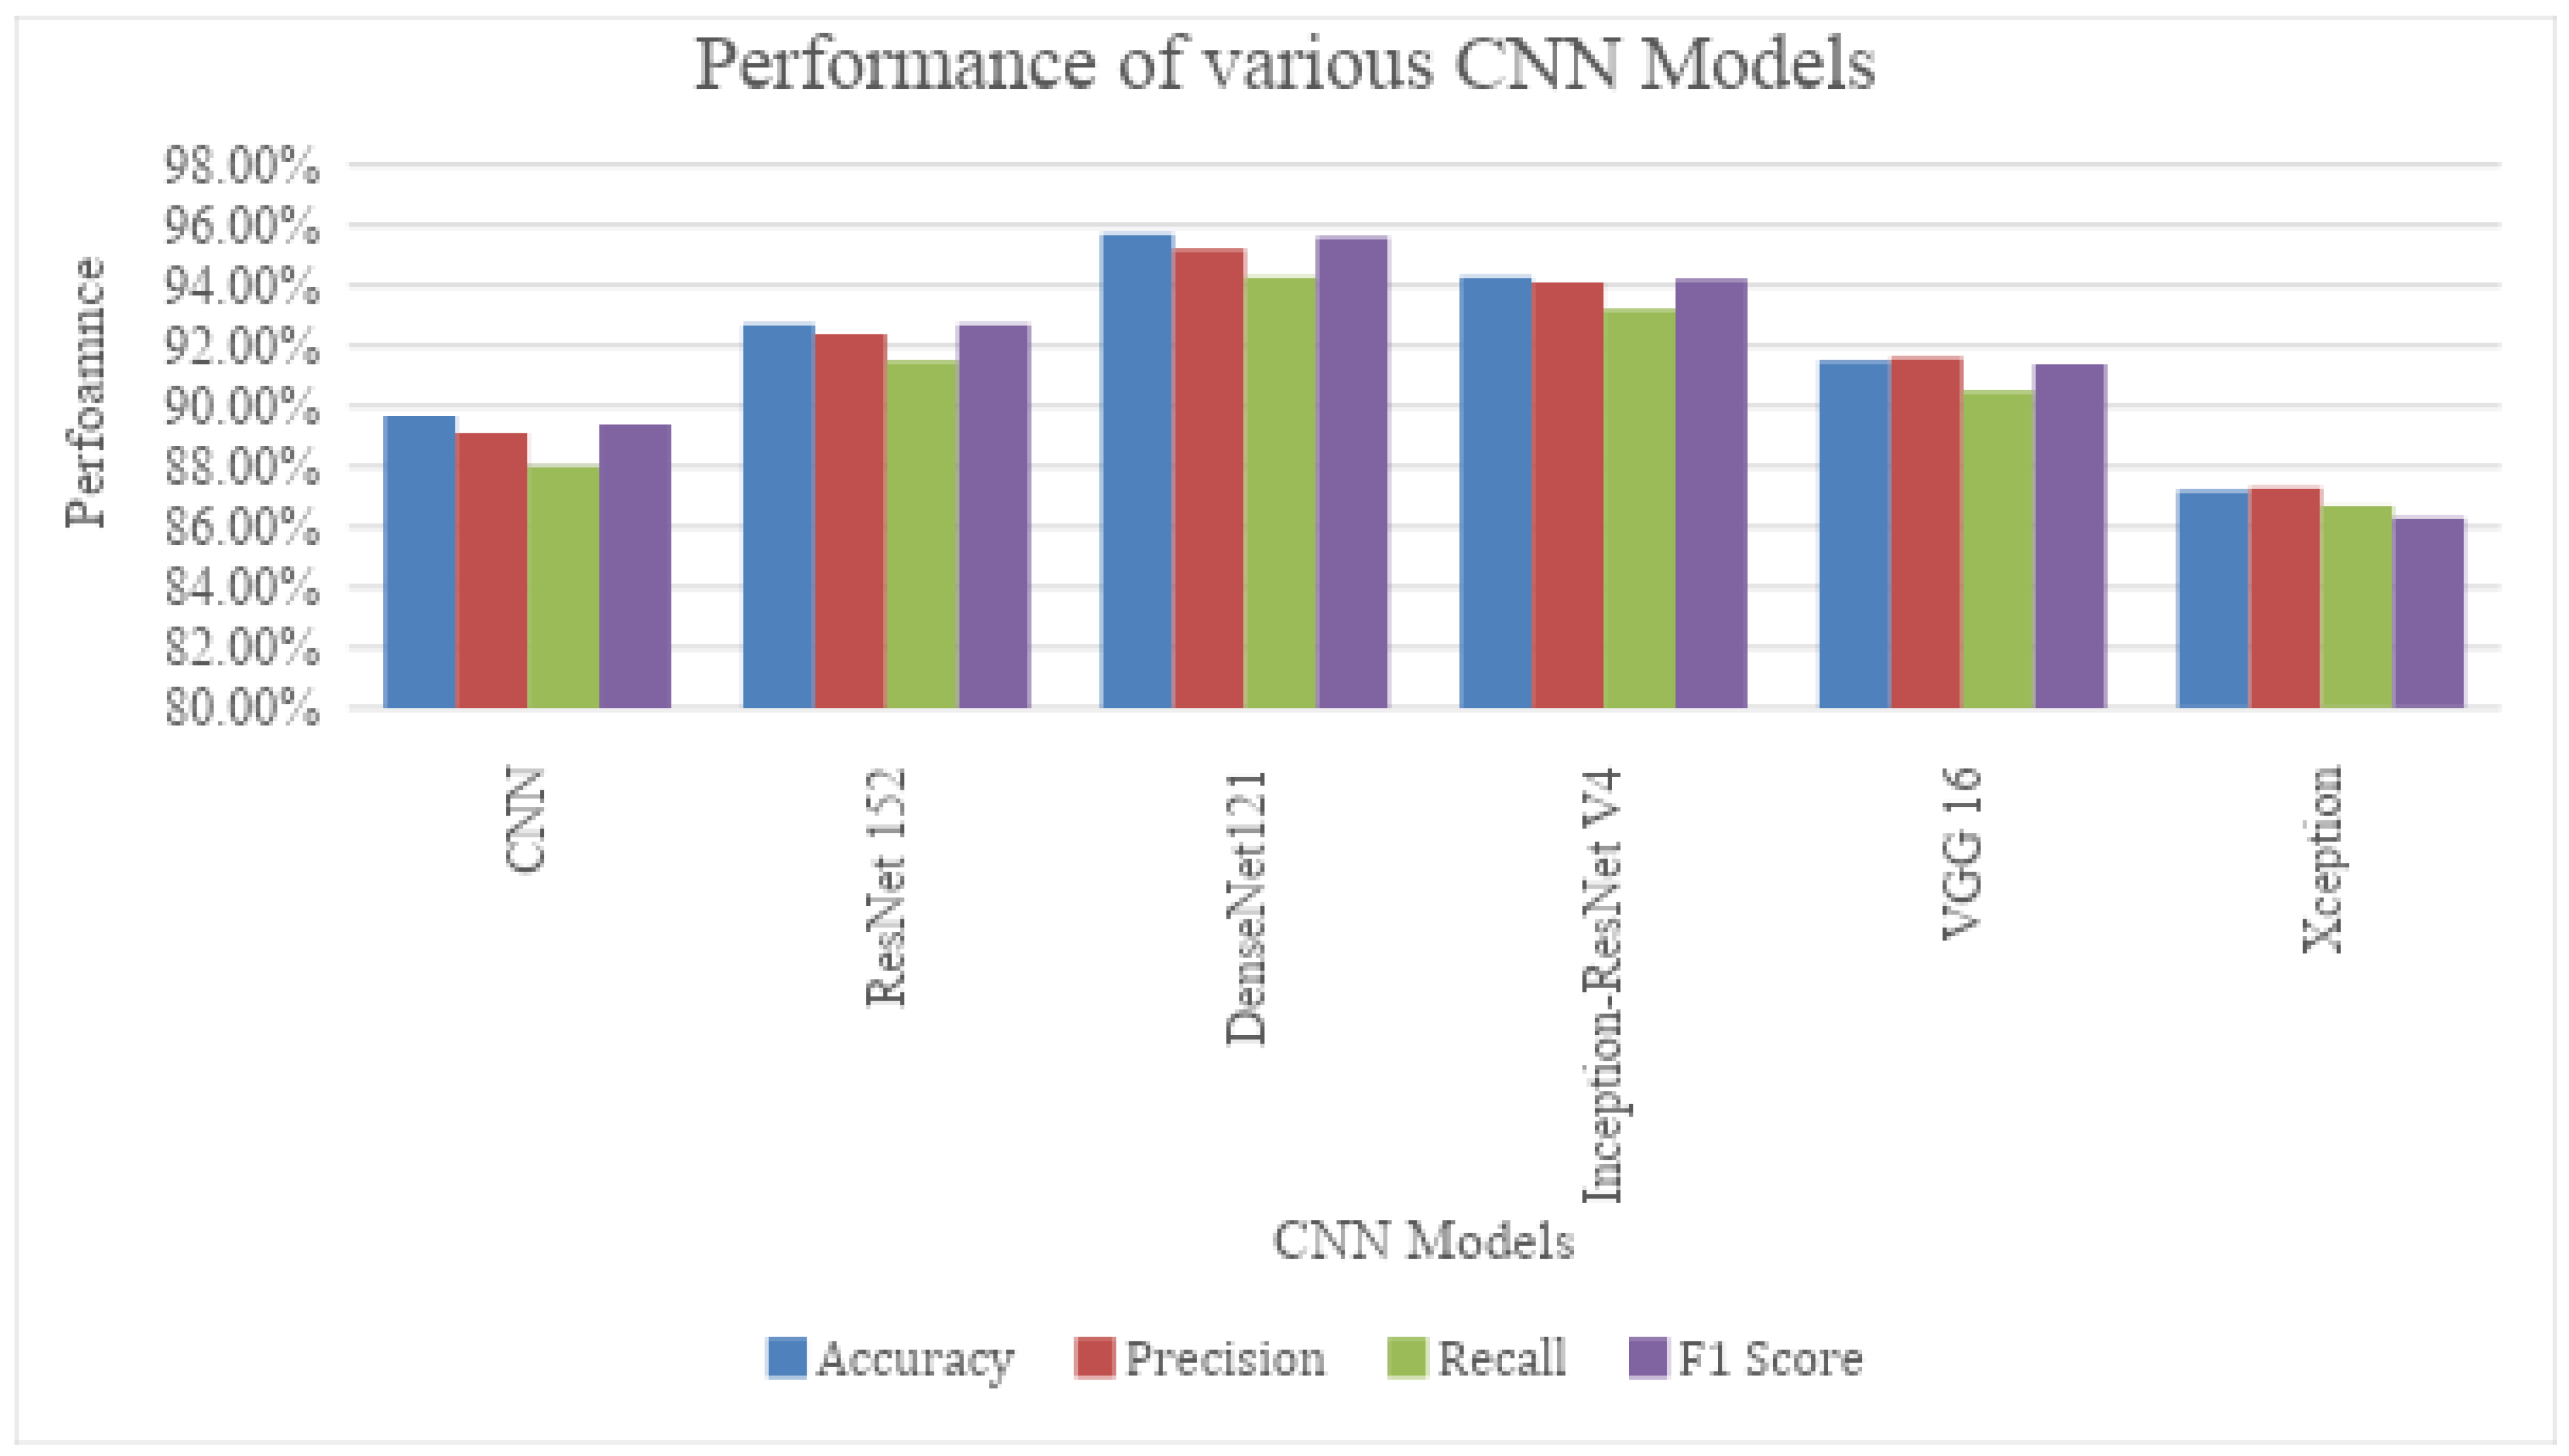

4.3. Classification Results Using Variants of the CNN Model

| Sl. No | CNN Architectures | Accuracy | Precision | Recall | F1 Score |

|---|---|---|---|---|---|

| 1. | CNN | 89.7% | 89.1% | 88.0% | 89.4% |

| 2. | ResNet 152 | 92.7% | 92.4% | 91.5% | 92.7% |

| 3. | DenseNet121 | 95.7% | 95.2% | 94.3% | 95.6% |

| 4. | Inception-ResNet V4 | 94.3% | 94.1% | 93.2% | 94.2% |

| 5. | VGG 16 | 91.5% | 91.6% | 90.5% | 91.4% |

| 6. | Xception | 87.2% | 87.3% | 86.7% | 86.3% |